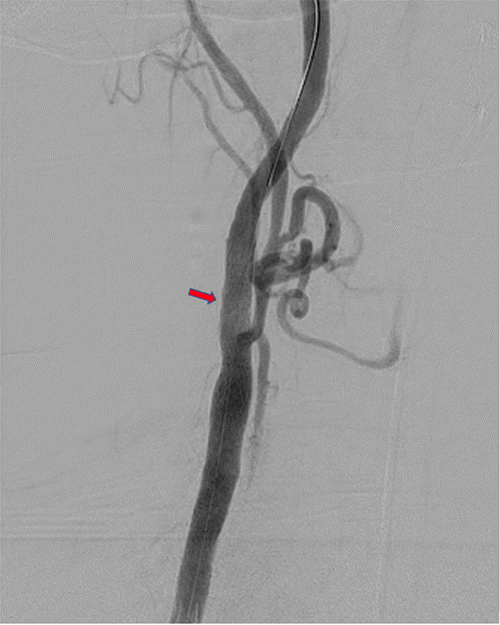

After expedited preoperative evaluation and medical optimization, the patient was taken to the hybrid suite for left TCAR under general anesthesia with cerebral oximetry. Carotid angiogram via direct proximal cervical common carotid artery exposure demonstrated severe focal ICA stenosis, corresponding with preoperative imaging (Figure 2A). After systemic anticoagulation and initiation of flow reversal via right femoral vein access, angioplasty of the left ICA was performed with a 5 × 20 mm balloon, followed by deployment of a 10 × 40 mm ENROUTE Transcarotid Stent (Silk Road Medical, Sunnyvale, CA) across the stenosis extending from the distal common carotid to the mid-ICA (in order to incorporate the ICA dissection). Completion angiogram demonstrated successful stent deployment with widely patent common, internal, and external carotid arteries (Figure 2B). The patient awoke without neurologic deficits. After surgery, he reported no headaches or further episodes of amaurosis fugax or other neurological events. Following one more day of blood pressure control management, he was discharged home with a prescription for clopidogrel. A plan was made for elective Right TCAR after a minimum of six weeks. The decision for a six-week interval was based on surgeon preference. While there is no conclusive data supporting simultaneous carotid interventions, many surgeons concur that waiting for recovery and monitoring hemodynamic and neurological function afterward may be safer, particularly for high-risk patients with severe stenotic lesions prone to reperfusion syndrome.

Figure 2. Left Carotid Angiogram During TCAR Procedure Before A) and After B) Angioplasty and Stent Deployment. Published with Permission

A.

B.